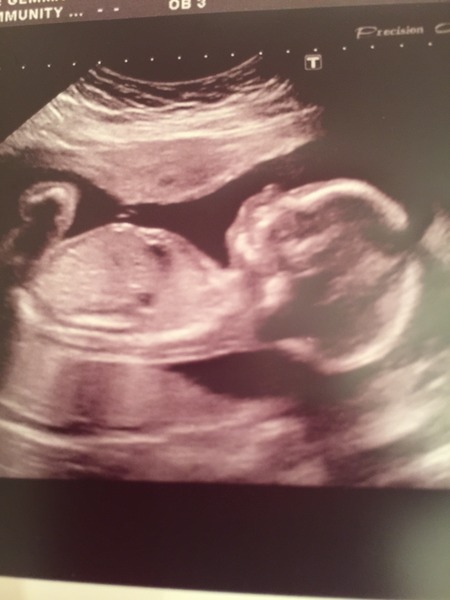

HopesAndDreams15 · 03/03/2016 20:24

Hello ladies,

A busy time for scans! Here's my little man today at our 20 week scan. All looking good Smile